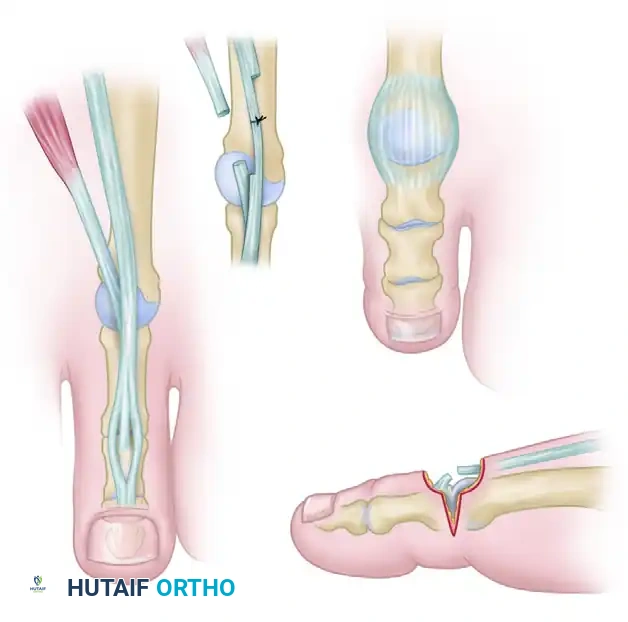

2. Tendon Lengthening and Resection

Correction of the hyperextension deformity at the MTP joint begins with addressing the contracted extrinsic and intrinsic extensor tendons.

- EHL Lengthening: Perform a Z-plasty lengthening of the EHL tendon. A 3-cm coronal Z-plasty is preferred over a sagittal cut, as the coronal plane allows for a smoother gliding surface post-repair and minimizes subcutaneous bulk.

- EHB and EDB Resection: Identify the EHB and EDB tendons, which lie immediately lateral and deep to the EHL and EDL as they approach the MTP joints. Excise a 5- to 8-mm section of both the EHB and EDB. Simple tenotomy is insufficient; a tenectomy prevents spontaneous reconstitution and recurrent contracture.

Clinical Pearl: Do not repair the EHL tendon at this stage. Keep in mind that overlapping the tendons during the final repair is much easier than discovering you have insufficient length when the MTP joint is later pinned or held in a neutral position.

3. Metatarsophalangeal Joint Capsulotomy

Assess the resting posture of the toes. The correction of the extension posture by tendon lengthening alone can sometimes be remarkable. However, if the deformity is not fully corrected to a neutral position at the MTP joint, a dorsal capsulotomy is required.

- With the EHL and EDL tendons retracted beneath the skin edges, sharply incise the dorsal capsule of the MTP joint.

- Release both the medial and lateral collateral ligaments at the MTP joint to allow the proximal phalanx to glide plantarly over the metatarsal head.

- Forcefully flex the MTP joint past neutral and dorsiflex the ankle to neutral. Observe the resting posture of the toes. If the MTP joint can now be flexed past neutral, turn your attention to the fixed contractures of the interphalangeal joints.

4. Management of the Hallux Interphalangeal Joint

If the IP joint of the great toe remains rigidly flexed, it must be addressed to prevent a "cock-up" deformity postoperatively.

- Approach the IP joint of the hallux through a separate L-shaped incision. The transverse limb of the "L" should be placed directly over the joint line.

Pitfall: The most common error during this approach is placing the transverse incision too far proximally, limiting joint access. Conversely, placing it too far distally risks irreversible damage to the germinal matrix of the nail.

- Incise the dorsal capsule, including the terminal tendon of the EHL, and release both collateral ligaments. Acutely flex the distal phalanx to open the joint.

- Using a Freer elevator, meticulously release the plantar plate from its proximal attachment on the proximal phalanx, and attempt to dorsiflex the IP joint to neutral.

- Decision Matrix for the IP Joint:

- If neutral position is attained: Maintain the IP joint in a straight position using two longitudinal transarticular Kirschner wires (K-wires) or a single obliquely placed wire.

- If neutral position cannot be attained: Proceed to an IP joint arthrodesis. Resect the articular cartilage and enough subchondral bone from both the proximal and distal phalanges to allow the joint to sit flush in a neutral position.

- Pinning Technique: Drive the K-wires retrograde through the distal phalanx so they emerge 2 to 3 mm plantar to the nail bed. Then, drive them proximally across the IP joint into the subchondral bone of the proximal phalanx.

Note: Occasionally, the K-wires must cross the first MTP joint for added stability, though a properly applied bulky forefoot dressing usually holds the MTP joint in the correct position without transarticular MTP pinning.